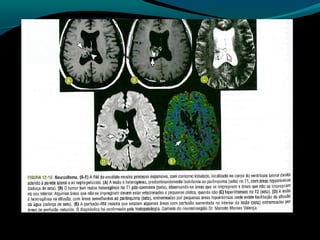

Glioblastoma

Maligno;

Origem astrocítica;

Grau IV;

60% dos astrocitomas;

15% das neoplasias intracranianas;

Mais frequente em adultos;

Sobrevida de 9 a 12 meses;

TC:

Geralmente supratentorial;

Infiltra substância branca;

Processo expansivo iso ou hipodenso de limites mal

definidos e necrose central;

Pode apresentar hemorragias;

Calcificações são raras;

RM:

Sinal heterogêneo em T1, T2 e FLAIR; (necrose, cistos,

hemorragia, neovascularização); mas predomina

hipointensidade em T1 e hiper em T2 e FLAIR;

Realce difuso e heterogêneo pelo Gd;